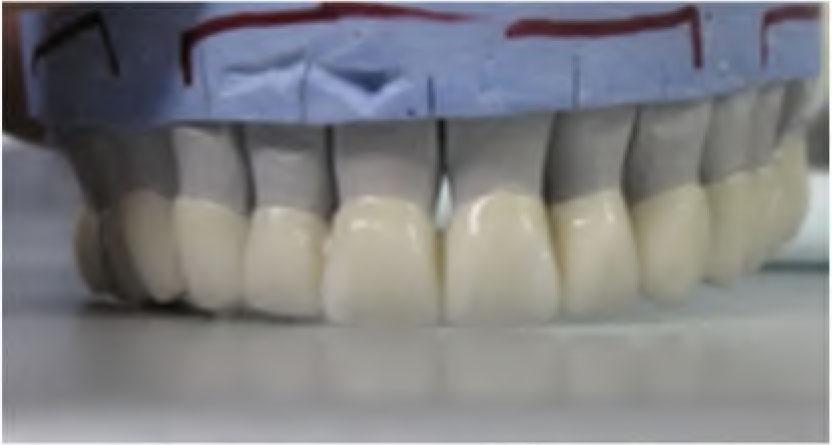

Then, the appropriate shade was selected using 3D-Master VITA guide (Vita Easyshade Compact, Vita Germany). Porcelain layering was made with porcelain VITA VM (9) (Vita Zahnfabric, Germany) (Figure 8 and 9).

All-ceramic FDP on dental cast model - frontal view